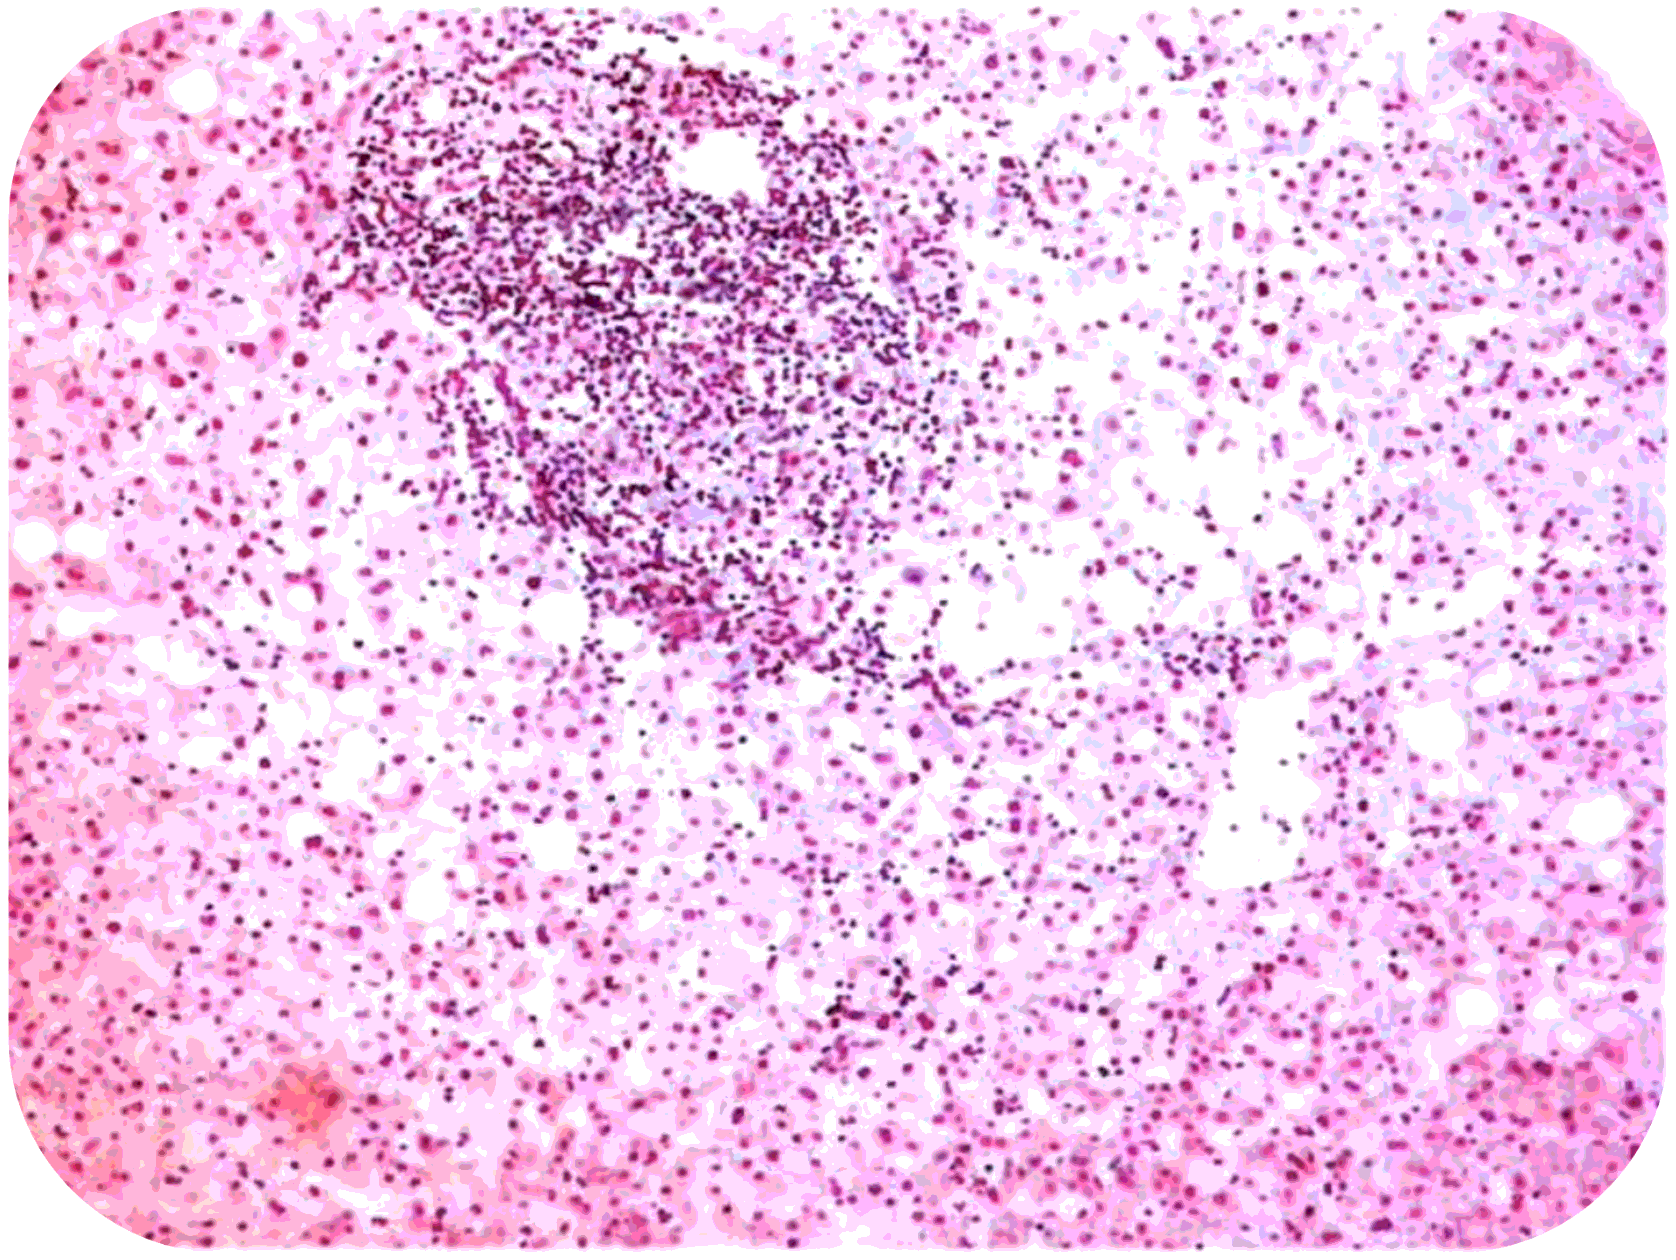

Преобладают гидроnическая и баллонная дистрофия геnа­тоцитов, в различных отделах долек встречаются очаговые (nятнистые) и сливные некрозы геnатоцитов (рис.1), тельца Каунсильмена в виде округлых гомогенных эозинофильных образований с nикнотичным ядром или без ядра- гепатоциты в состоянии коагуляционного некроза с резко уменьшенными органеллами, или «мумифицированные» гепатоциты.

Cливные некрозы геnатоцитов

Рис 1. Острый вирусный геnатит (биоnсия nечени).

Баллонная дистрофия и некроз геnатоцитов

Портальная и внутридольковая стромы диффузно инфильтрированы лимфоцитами и макрофагами с примесью плазматических клеток, эозино- и -нейтрофильных лейкоцитов. Количество звездчатых ретикулоэндоте­лиоцитов значительно увеличено.

Клетки инфильтрата выходят из порталь­ной стромы в паренхиму дольки и разрушаются гепатоциты пограничной пластинки, что ведет к появлению ступенчатых перипортальных некрозов. В различных отделах долек много переполненных желчью капилляров.